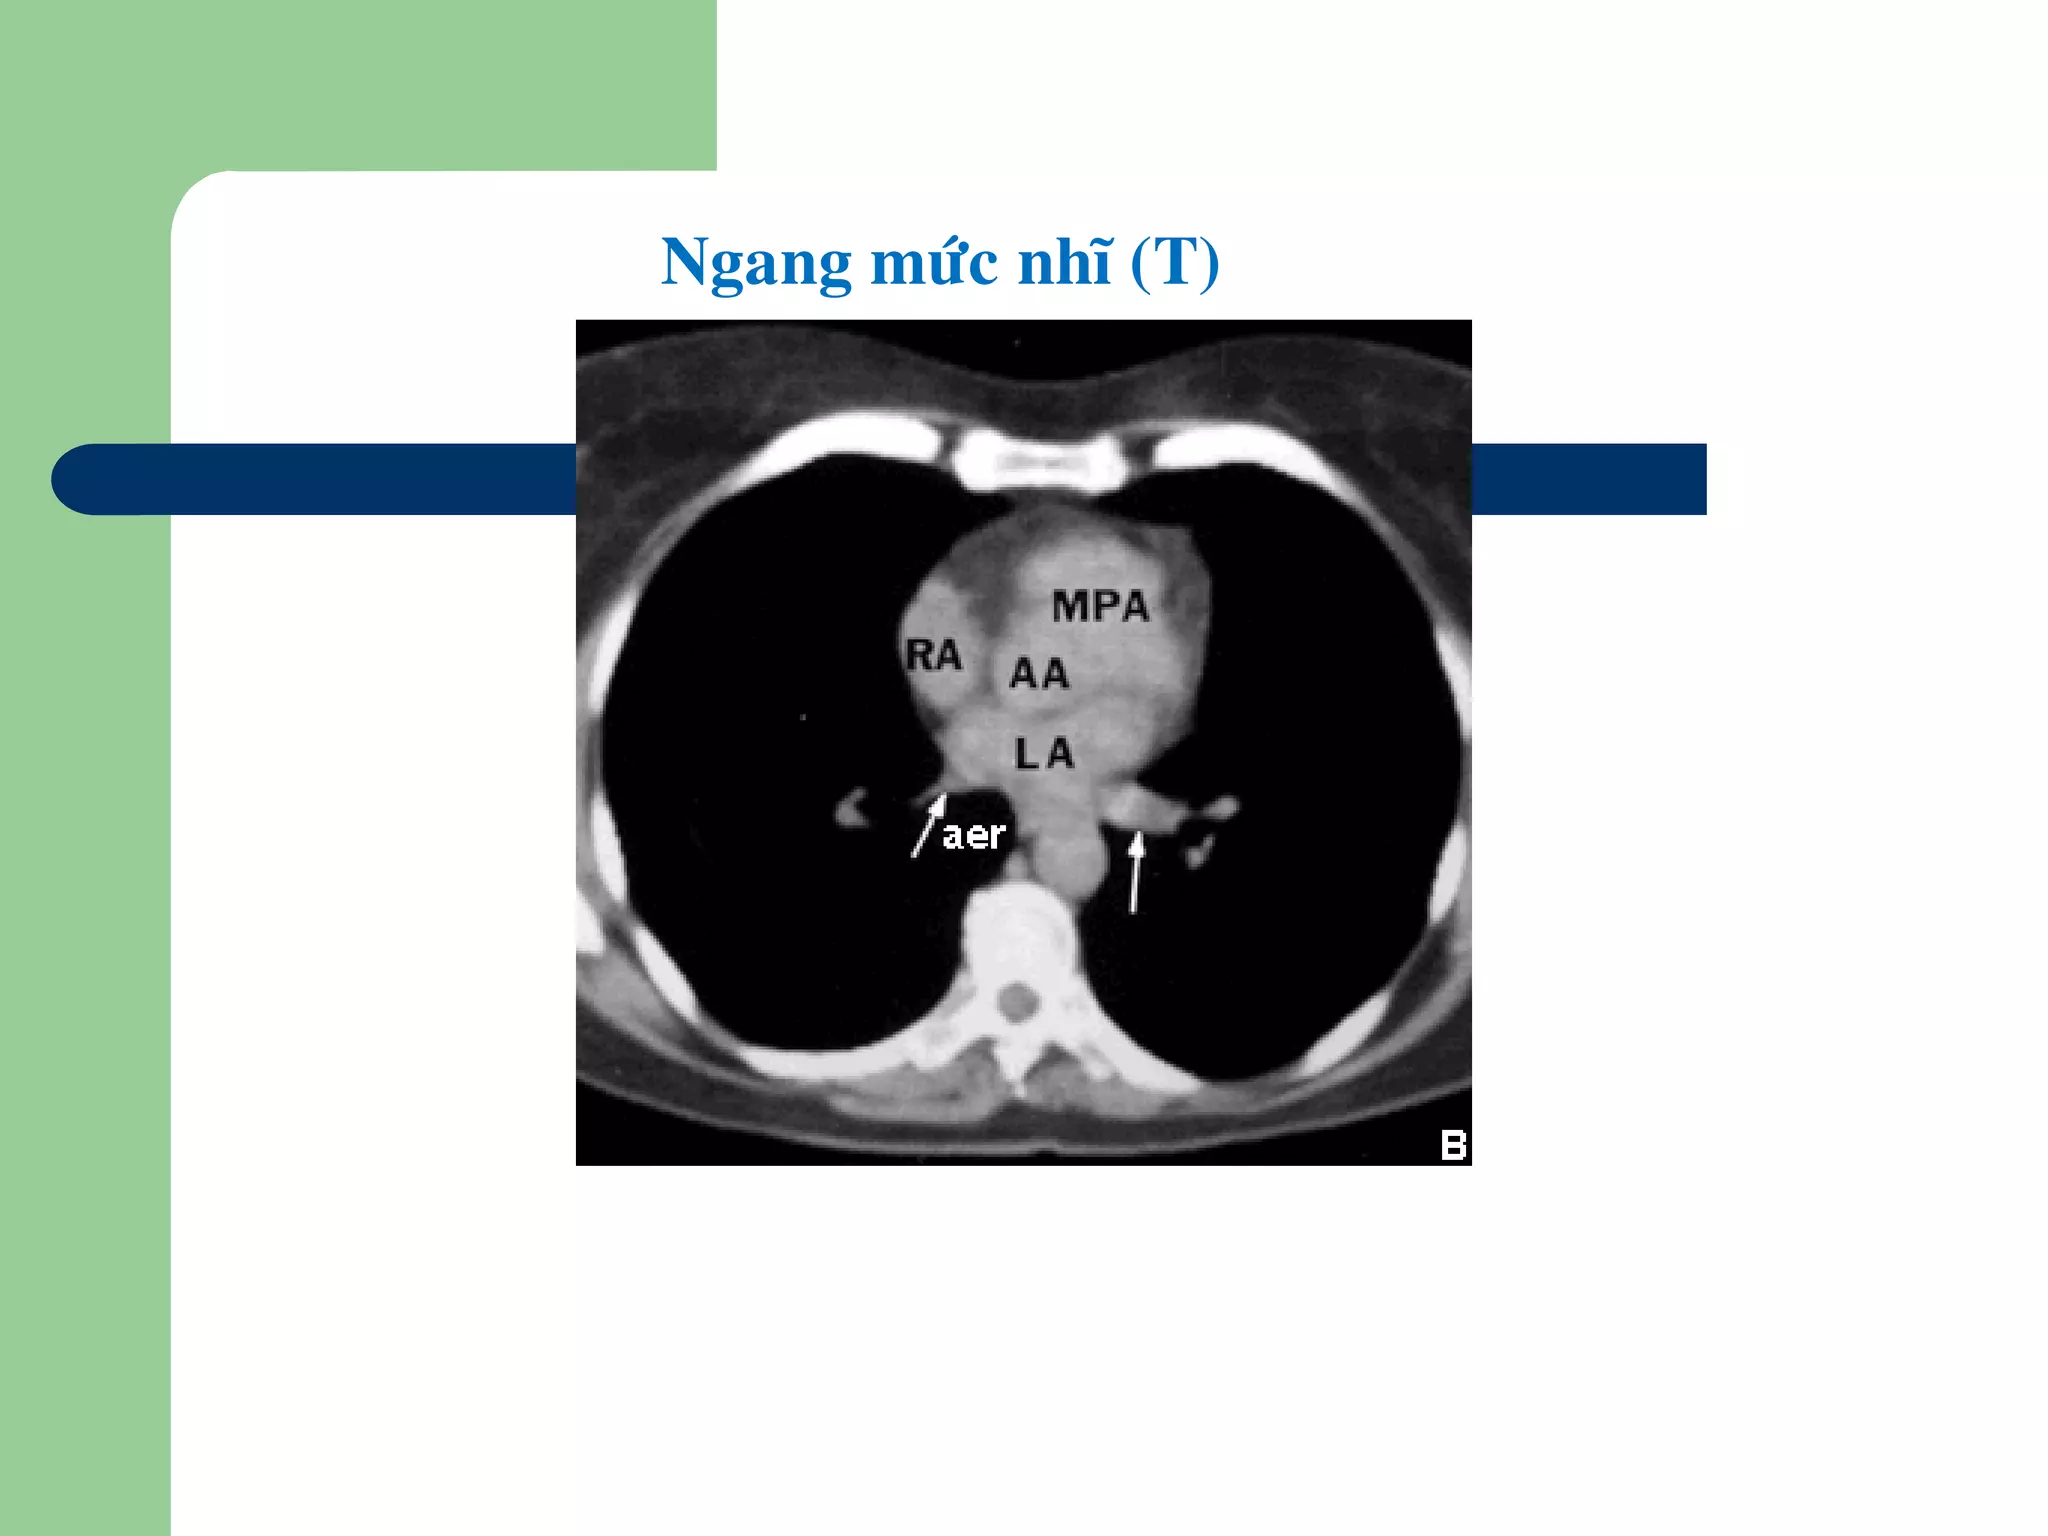

Ngang möùc nhó (T)

Ngang möùc ñoäng maïch phoåi (P) vaø thaân

ñoäng maïch phoåi

•Ñoäng maïch phoåi (P) [RPA] töø thaân ñoäng maïch phoåi

[MPA], chaïy sang (P) phiaù sau ñoäng maïch chuû leân

[AA]